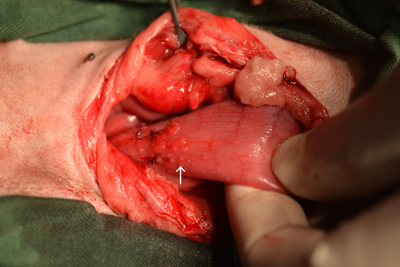

当院での症例のご紹介 みなみ野動物病院 八王子みなみ野。

Case50 試験開腹で反応性肉芽組織と診断された腹腔内腫瘤の犬の1例 –つつじヶ丘動物病院東京都調布市の動物総合病院。一般診療、循環器科、腫瘍科など。

Case50 試験開腹で反応性肉芽組織と診断された腹腔内腫瘤の犬の1例 –つつじヶ丘動物病院東京都調布市の動物総合病院。一般診療、循環器科、腫瘍科など。